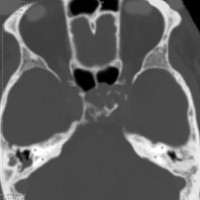

骨をみているCTです。鞍背からsphenooccipital synchondrosisまでの斜台骨皮質が失われています。かなり特徴的な所見です。